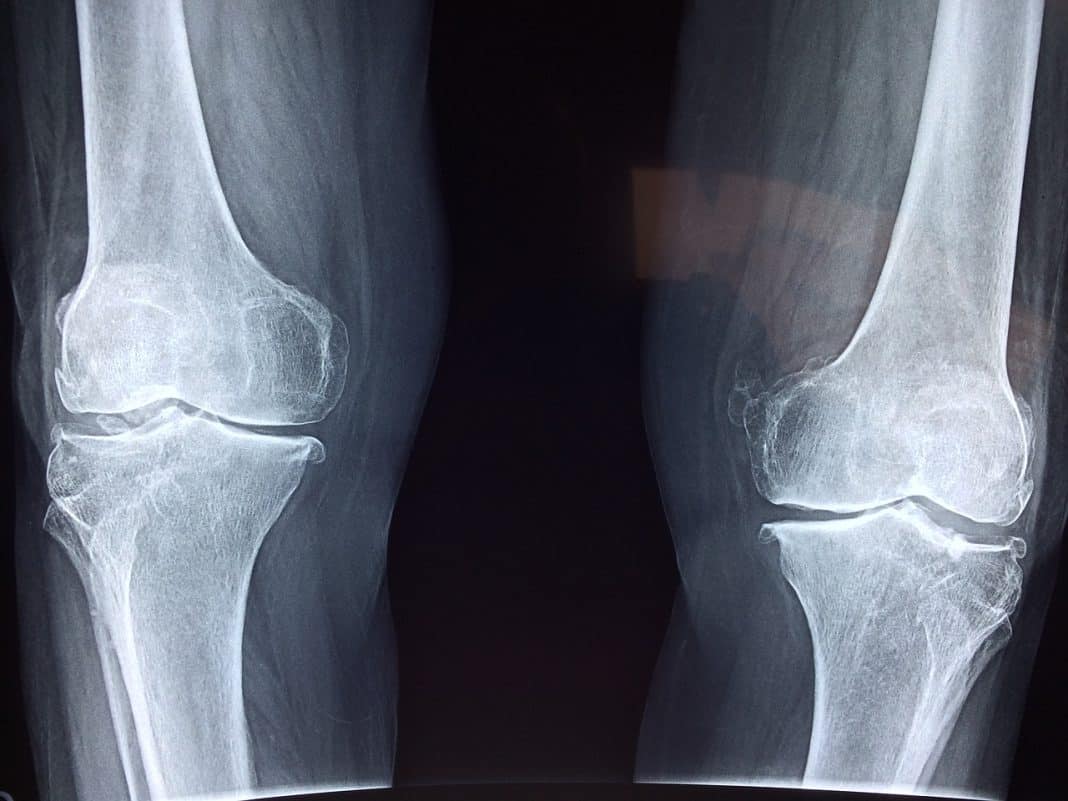

Las moléculas de la mucosidad pueden utilizarse para producir material sintético de injerto óseo y ayudar en la curación de grandes pérdidas óseas. De esta manera, se pueden contribuir a la curación de lesiones graves en los huesos. Esta innovación abre nuevas posibilidades en el campo de la biotecnología médica.

El desarrollo de un gel bioactivo es una nueva esperanza para tratar las pérdidas óseas, ya que se espera que mejore los resultados actuales. Este enfoque se basa en utilizar material sintético combinado con células propias del cuerpo. Lo que aumenta la eficacia de la curación.